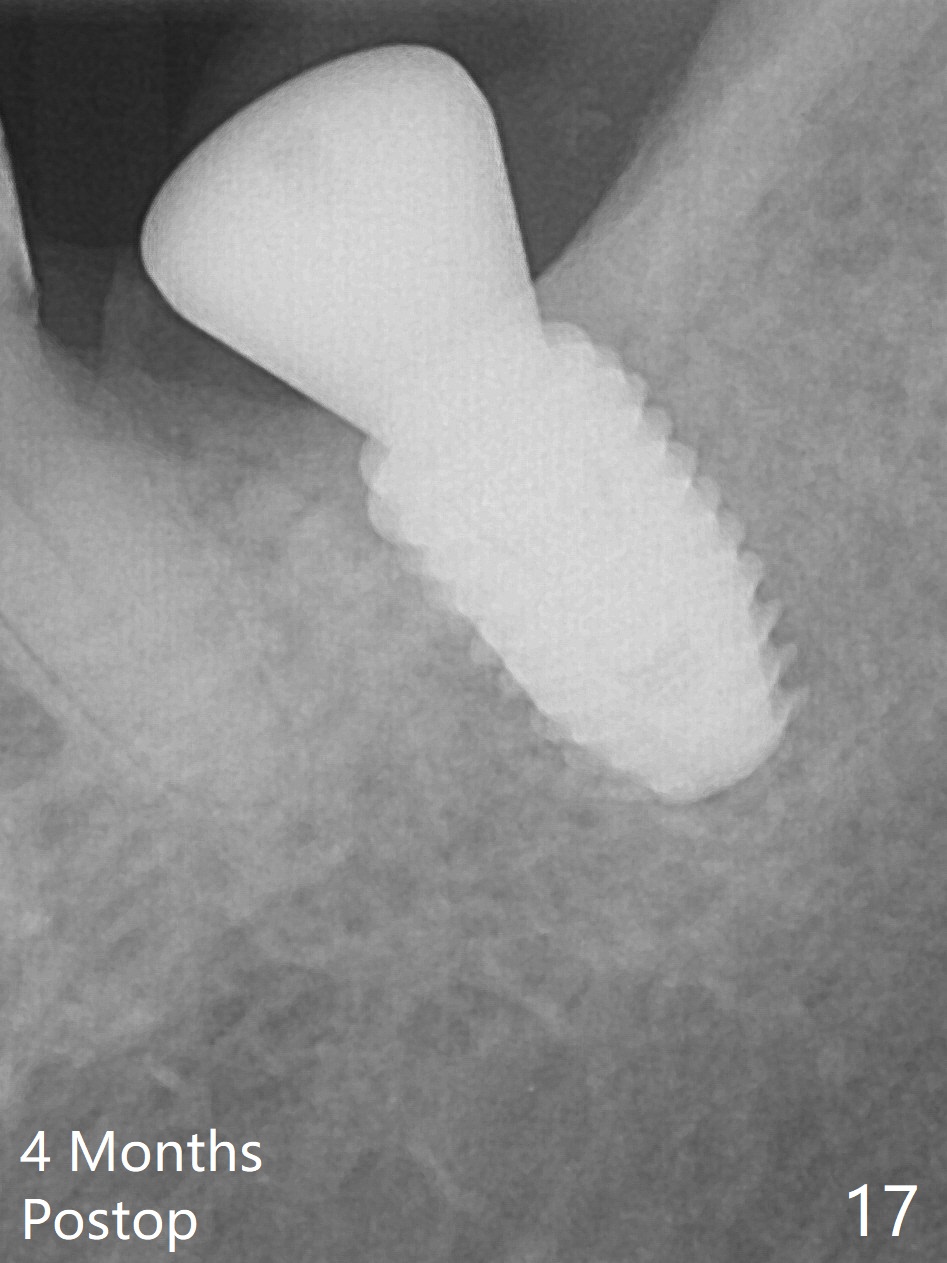

There is no apparent bone loss 4 months postop (Fig.10). There is chewing pain in spite of occlusal adjustment 7 months post cementation (Fig.11-13: increased radiolucency around the implant). The crown/abutment is removed and a healing abutment is placed (6x3 mm); the implant is stable. The patient return for re-evaluation in 3 months (15 months postop); radiolucency appears to reduce (Fig.14). But there is pain when the healing abutment is being removed. After local anesthesia, the implant is removed with a wrench. Following debridement of the osteototomy (intact, although tender), a 5x10 mm dummy implant with SLA surface is placed (Fig.15). After 5.5 mm tap, a 5.5x8.5 mm implant is placed with >50 Ncm (Fig.16). A 6.8x5 mm healing abutment is placed, followed by periodontal dressing. Re-analysis of preop CBCT shows that the bone density at the site is low: 70 units average. Progressive loading is necessary for this case 4-6 months postop. The soft and hard tissues around the implant seem to heal 4 months postop (Fig.17).